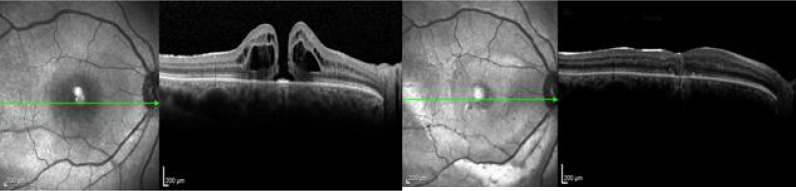

Background: Present a new surgical technique which involves using pars plana vitrectomy (PPV) combined with a free internal limiting membrane (ILM) flap anchored by an intraoperatively obtained blood clot, assisted by intraoperative optical coherence tomography (i-OCT).

Methods: This is a prospective interventional non-comparative study with three cases of recurrent or refractory macular hole treated with a new surgical technique using autologous blood clot obtained from the retinal vessels.

Results: This study included 3 eyes of 3 patients. All patients were previously treated with a PPV and internal limiting membrane peeling. One week post-operatively, all operated eyes showed closure of the macular hole. No complications secondary to the surgical technique occurred.

Conclusion: This is a small case series that obtained anatomical success in the macular hole closure with a reproducible technique involving the use of i-OCT to position a free ILM flap, anchored by a blood clot obtained from per operatory retinal bleeding. Further controlled research needs to be done to prove the efficacy.